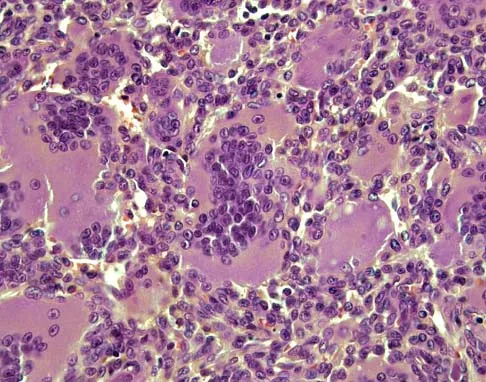

Figure 26a shows the radiograph of a 55-year-old woman who has pain in her right leg after falling. Laboratory studies reveal an elevated alkaline phosphatase level. A biopsy specimen from the proximal tibia is shown in Figure 26b. What is the most likely diagnosis?